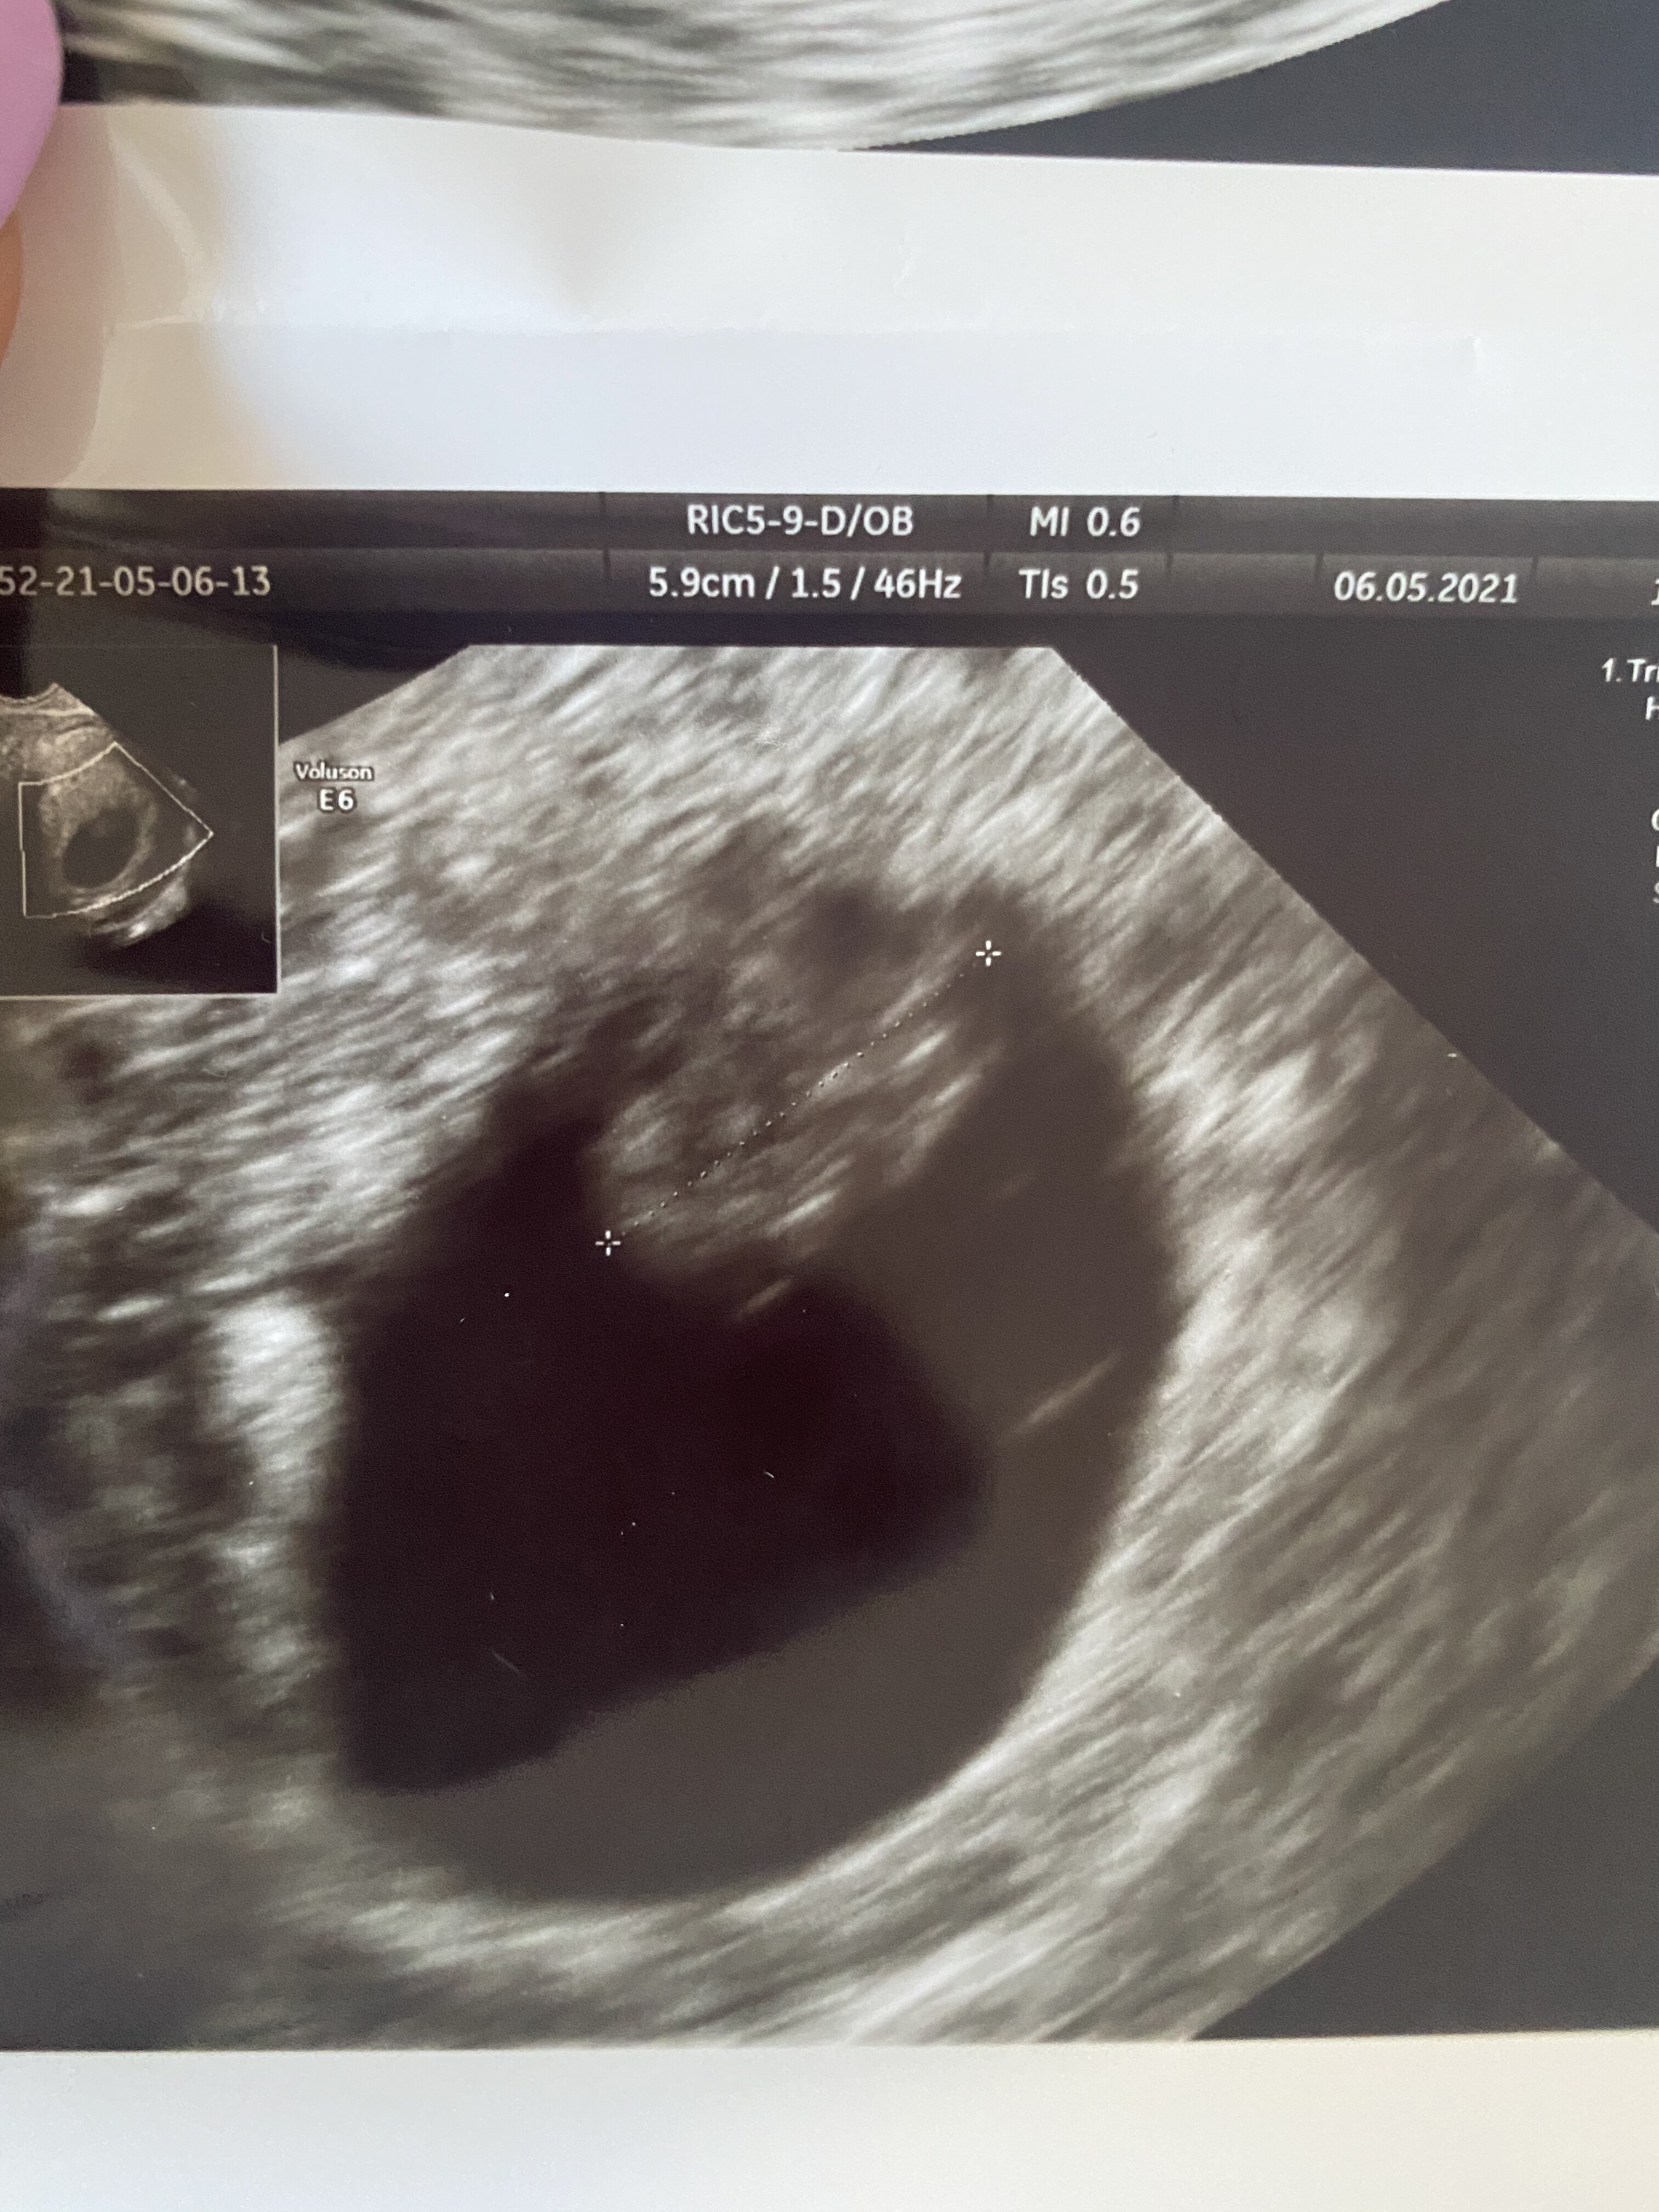

Byłam już na dwóch badaniach USG i ciąża jest w macicy, a zarodek w pęcherzyku, tyle że nadal nie słychać serduszka. Więc jeśli już, to raczej to ostatnie wchodzi w grętrochę za mało szczerze, powtórz ta betę raz jeszcze dla swojego bezpieczeństwa za dwa dni, małe przyrosty i utrzymujące się słabo rosnące beta hcg to tez może być pozamaciczna, są sytuacje, ze pęcherzyk w macicy, a zarodek gdzies indziej, rzadko bardzo się to zdarza, ale zdarza, albo beta Ci już leci w dol po prostu

Uff byłam i wszystko ok

serducho bije, z usg 7+2, mam się nie stresować, objawy mogły już mi minąć

mówi, ze wszystko już będzie dobrze bo to już duże dziecko, ma 1,14 cm